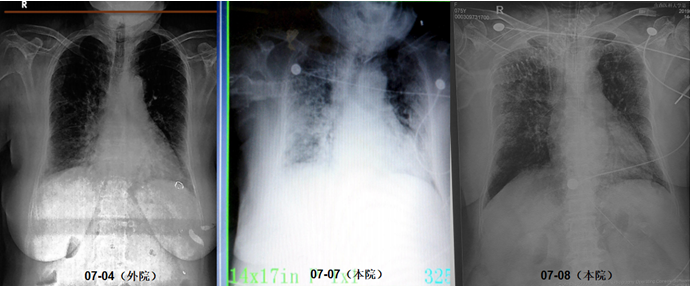

尿军团菌抗原(+)。入院第2天:无创机械通气通气,FiO2 100%;第3天气管插管,有创机械通气,FiO2 100%,PEEP 13 cmH2O。第4天,FiO2 45%,PEEP 8 cmH2O。逐渐降低支持力度,插管第7天撤机,拔管。拔管5天转入普通病房。整个病程中患者发热症状持续14天。患者入院前后胸部影像学变化如图2所示。

图2  患者胸部CT变化

抗感染方案:①头孢哌酮他唑巴坦+莫西沙星+阿奇霉素;②替加环素+莫西沙星;③替加环素+莫西沙星+卡泊芬净(痰培养提示热带假丝酵母菌);④莫西沙星。

经过治疗,患者胸部CT仍可见双肺斑片状磨玻璃渗出影,但整体情况尚可,遂予拔管。出院前复查胸部CT可见病灶明显吸收,下肺有少许纤维条索状渗出(图3)

图3  患者胸部CT